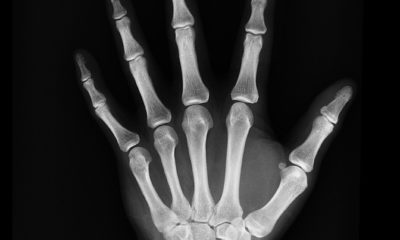

Степень облучения пациента после применения различных видов рентгенологической диагностики в медицине.

Где применяется рентгеновское обследование и его разновидности, зависящие от диагностических или лечебных задач.

Рентгенография — метод рентгенологического исследования, при котором с помощью рентгеновского излучения на чувствительном к нему материале, как...